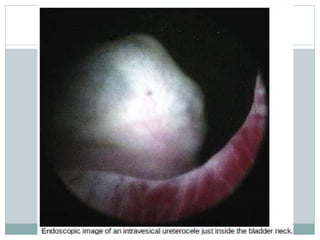

ENDOSCOPIC EVALUATION:

 Assess character of urethra, bladder neck and trigone

relative to ureterocele or ectopic ureter.

 Location of other ureteral orifices should be documented.

 Orifice of affected ureter should be sought but may not be

identified.

 Urethra is examined carefully for orifice if not seen in

bladder.

 Appearance of ureterocele will vary with bladder filling;

start with little filling and slowly increase bladder volume.

 Lowest portion – best site for incision.

 Retrograde contrast can confirm ureterocele disproportion

& unusual connections with genital ducts.